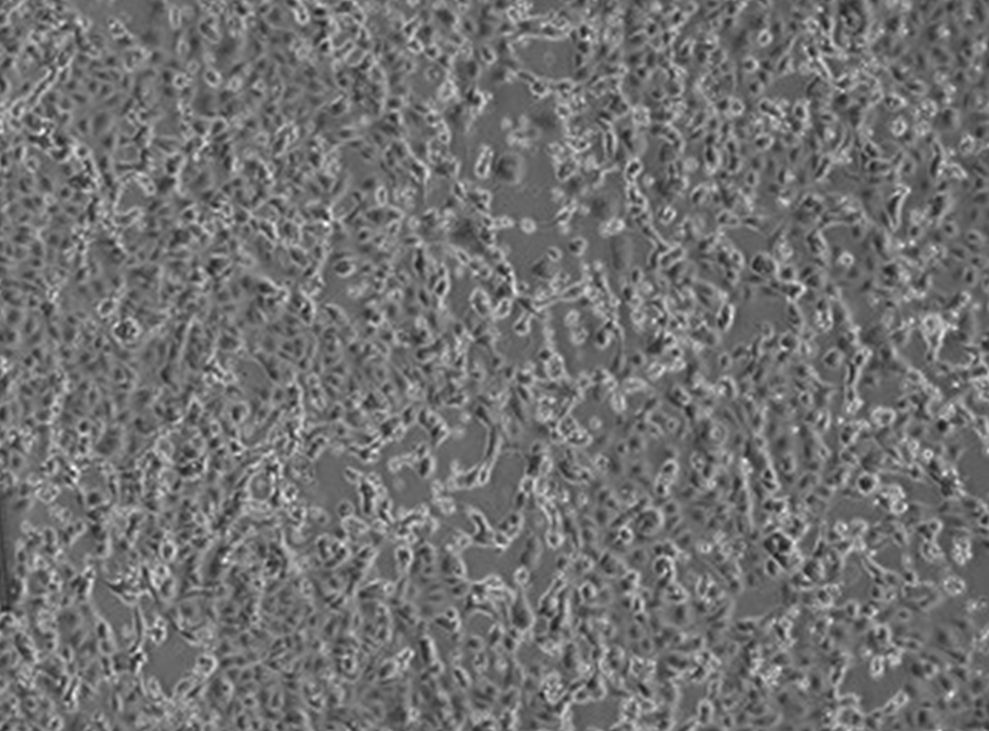

ROMA (ITALPRESS) – I virologi dell’Istituto Nazionale Malattie Infettive “Lazzaro Spallanzani”, a meno di 48 ore dalla diagnosi di positivita’ per i primi due pazienti in Italia, sono riusciti, primi in Europa, a isolare il virus responsabile dell’infezione.

Avere a disposizione il virus e’ un passo fondamentale che permettera’ di perfezionare i metodi diagnostici esistenti ed allestirne di nuovi. Inoltre permettera’ di studiare i meccanismi della malattia per lo sviluppo di cure e la messa a punto del vaccino. La sequenza parziale del virus isolato nei laboratori dello Spallanzani, denominato 2019-nCoV/Italy-INMI1, e’ stata gia’ depositata nel database GenBank, e a breve anche il virus sara’ reso disponibile per la comunita’ scientifica internazionale.